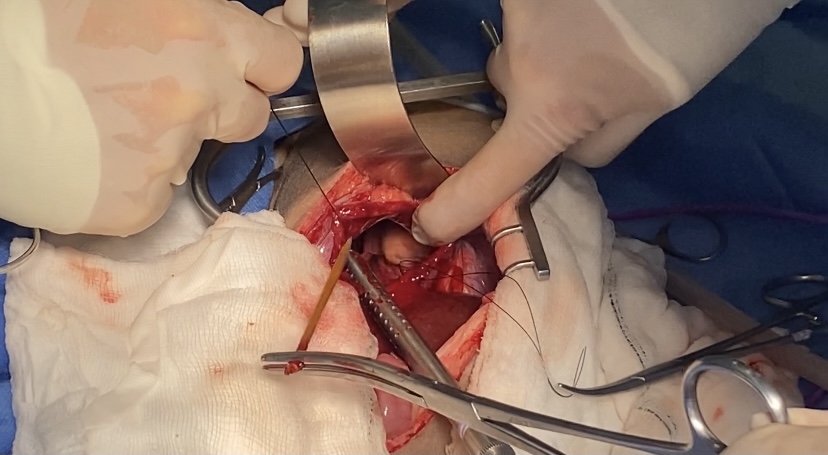

Vets at an award-winning animal hospital in Yorkshire have successfully removed a huge 5kg tumour from a cancer-stricken Dalmatian.